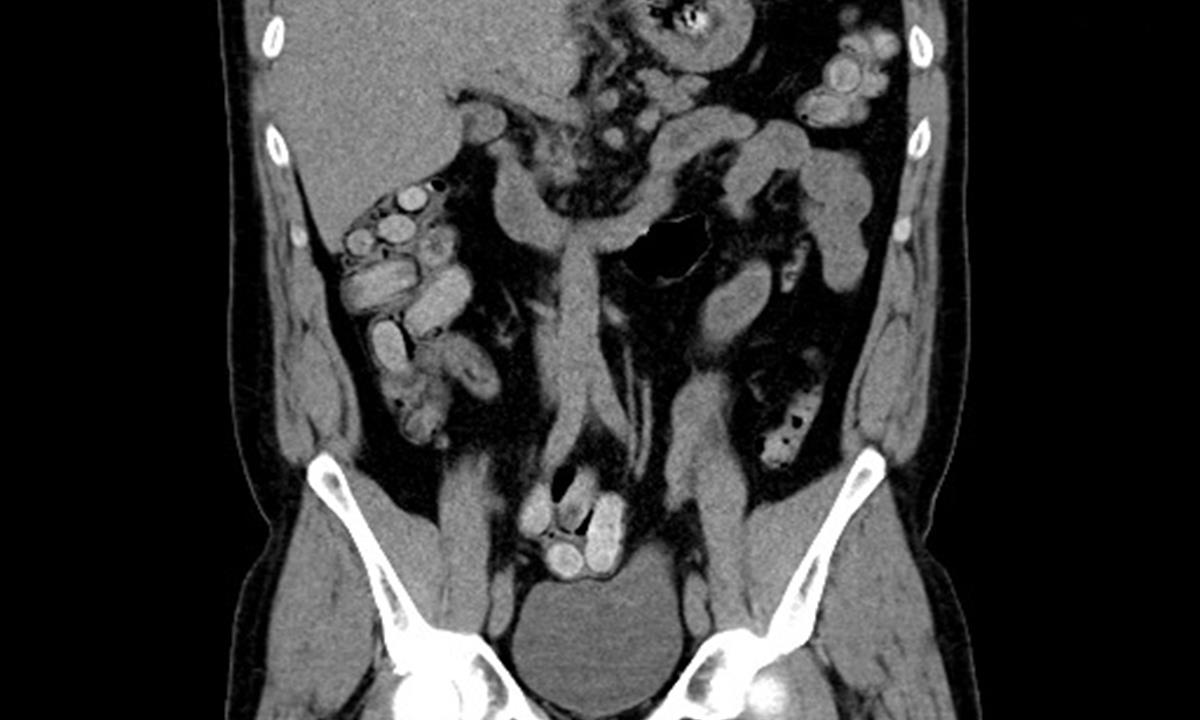

Celníci muže zadrželi a převezli na odborné lékařské vyšetření – počítačovou tomografii (CT). Snímky z CT prokázaly, že se v jeho břišní dutině nacházejí desítky kapslí o velikosti 2x5 cm s neznámým obsahem.

Již během sobotní noci vyšlo na speciální toaletě z těla pašeráka prvních 26 kapslí obsahujících kokain. Další kapsle vycházely postupně v následujících dnech, poslední v úterý večer. Dnešní kontrolní CT vyšetření potvrdilo, že se v jeho tělních dutinách již žádné kapsle nenacházejí.